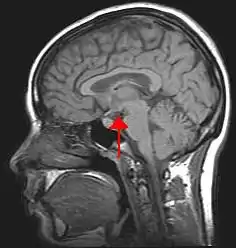

Location of the human hypothalamus

Location of the hypothalamus (blue) in relation to the pituitary and to the rest of the brain